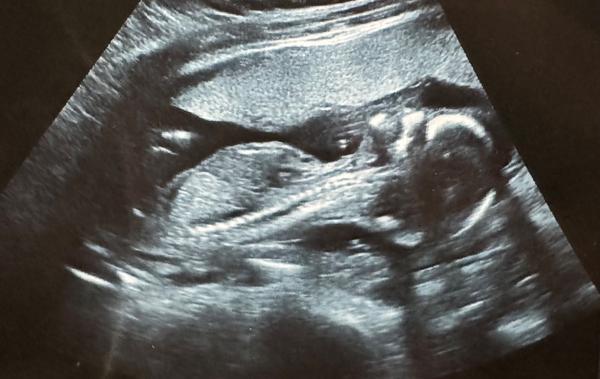

Ahoj, musela bys mít fotku přímo pohlavních orgánů. Tady nic není vidět. Počkej si na 2. screening. Do té doby se nám mimčo také nechtělo ukázat.